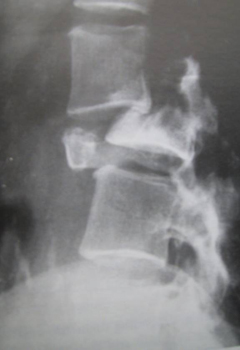

- plain x-rays